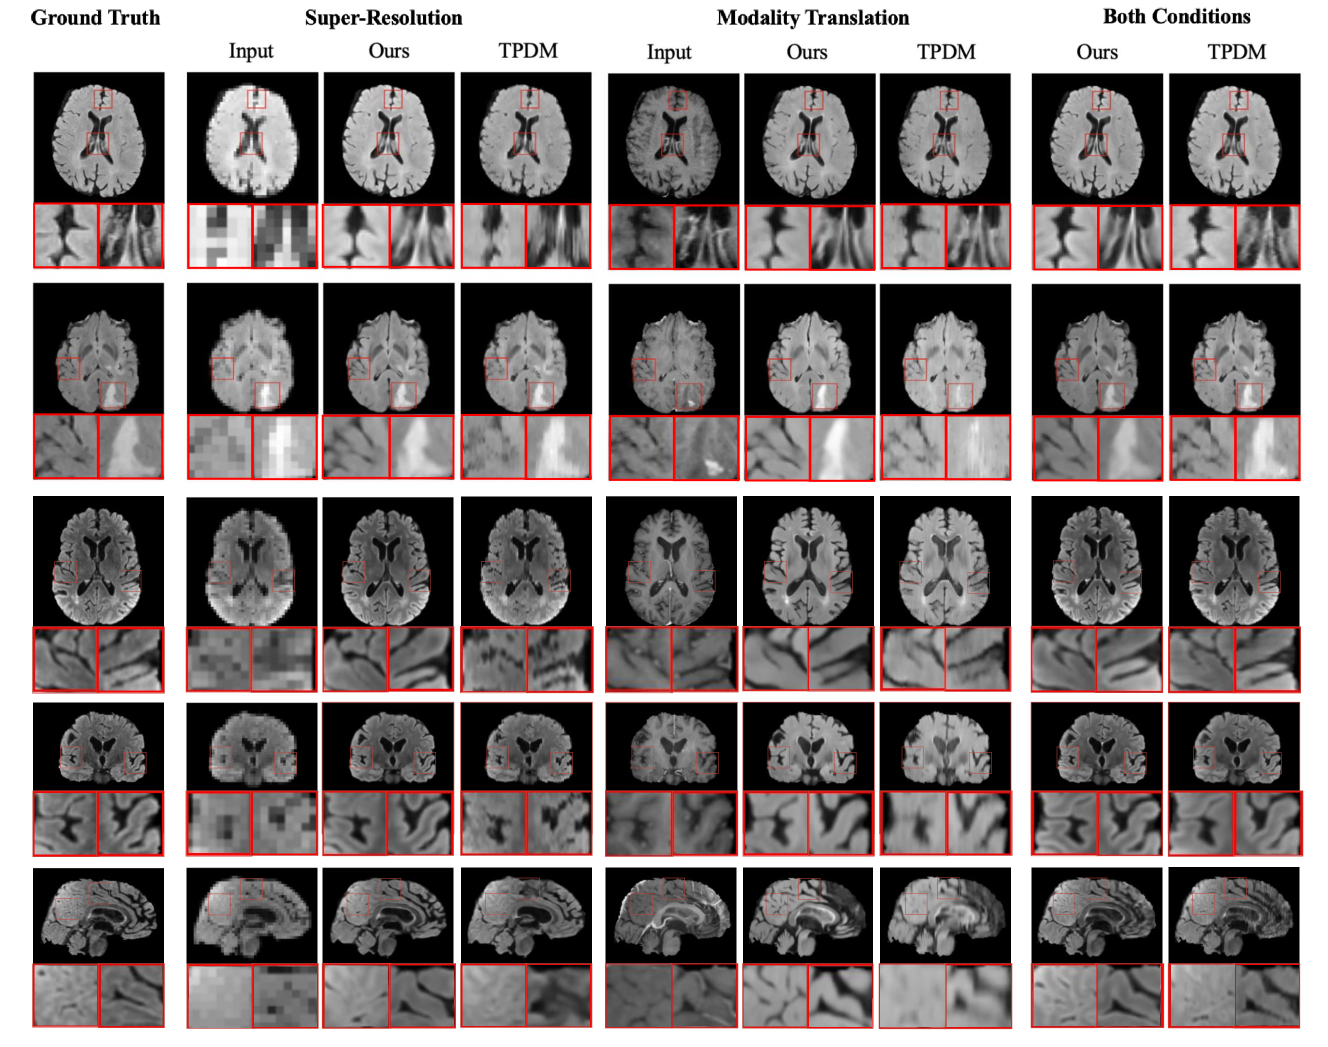

Refer to caption

Figure 3: Visual comparison of generated samples for three different conditions. The first three rows show axial view slices from different MRI volumes. Neither Score-Fusion nor TPDM have a 2D model trained in this direction. The last three rows show slices for the same MRI volume in all three views. Score-Fusion reconstructs more realistic details with smoother edges and fewer artifacts.

We showcase the performance of Score-Fusion in solving various translation problems, including 4×\times× super-resolution, modality translation, and a fusion of both conditions in Fig. 3. We also include more randomly selected samples for more variants of our model in Sec. C. Fig. 3 shows the generation quality under various conditions and provides comparisons with other methods. The first two columns show the performance for super-resolution and modality translation, and the last columns show the model performance when fusing these two conditions. Our approach excels in faithfully recovering intricate high-frequency details, particularly in tumor-affected areas where such details are complex and often underrepresented. In the super-resolution task, from the zoomed-in panel, Score-Fusion clearly distinguishes tissue boundaries across various tissue types, including tumor and white/grey matter. In the modality translation task, the distribution of contrast difference between modalities is also better captured, as stated in Sec. B. Furthermore, our method demonstrates superior volumetric consistency, while the baseline model exhibits noticeable artifacts. In the visualization of Score-Fusion, the fidelity of tissue texture and sharpness along all three orthogonal directions are well preserved, even though the 2D diffusion models in Score-Fusion are trained only on transverse and sagittal planes. Our model reconstructs tumor regions with clearer margins, fewer artifacts, and higher resolution for samples containing tumors, providing superior performance in all three orthogonal directions. Overall, Score-Fusion generates images with higher accuracy, realism, and volumetric consistency. Tab. 1 summarizes the quantitative results of each translation task. Score-Fusion clearly surpasses other baseline models in most metrics, showing superior fidelity, structure, texture preservation, and noise suppression performance.